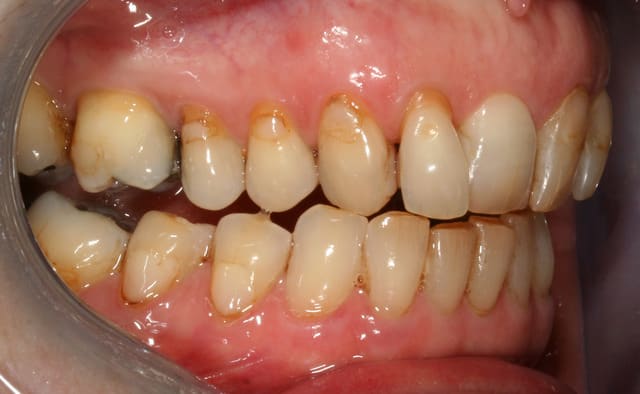

cette patiente que je suis en controle depuis 2 ans, se décide à faire quelque chose pour son sourire.

grosso modo depuis 2 ans, pas de soucis particuliers, pas de caries, faut faire un peu gaffe à la paro mais elle est plutôt motivée et ça se passe bien.

elle a plein de vieux compos d'une mauvaise couleur, au joints colorés, des dents de couleur pas vraiment toutes pareilles ; et un sourire très gingival.

je ne sais pas trop d'ou ça viens, de mylolyses traitées au compo ou d'un épisode de caries au collet ?

elle ne fume pas, bois du thé, un peu de café.

pour l'occlusion, voilà les photos, il y a effectivement une classe II, plus marquée à droite qu'à gauche

il y a l'absence de la 36 depuis quasiment l'enfance, l'occlusion est calée comme ça depuis plus de 30 ans et ça ne bouge pas